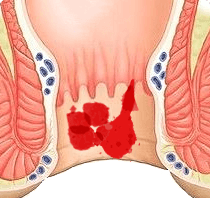

La cosa principale del problema delle emorroidi è che in nessun

caso dovrebbe essere trascurato. Non appena compaiono i primi

sintomi, è necessario iniziare a combattere il problema. Lo

stile di vita e la nutrizione sono importanti, ma se i sintomi

delle emorroidi sono già comparsi, solo queste misure non

aiuteranno. Se non ti accorgi in tempo, purtroppo, solo la